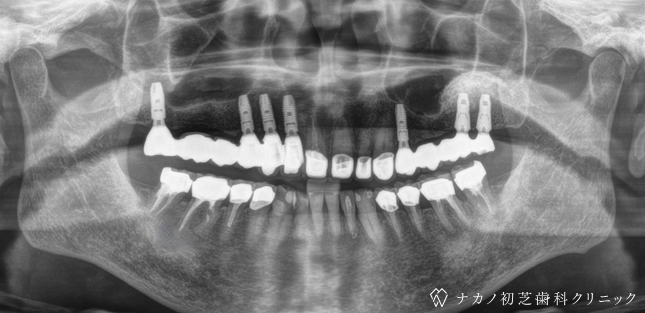

インプラント・13本 (60代女性)

BEFORE

AFTER

年齢 60代女性

治療内容 インプラント治療13本(骨造成の併用)

インプラント治療とは、歯を抜いた所にチタン製の人工歯根を埋入し、その上に歯を入れる方法です。骨を増やすことで、より審美的に治療が出来ました。費用 1本 400,000円(税込 440,000円)

リスク・副作用

腫れ・疼痛・違和感を感じるなどの症状を生じることがあります。